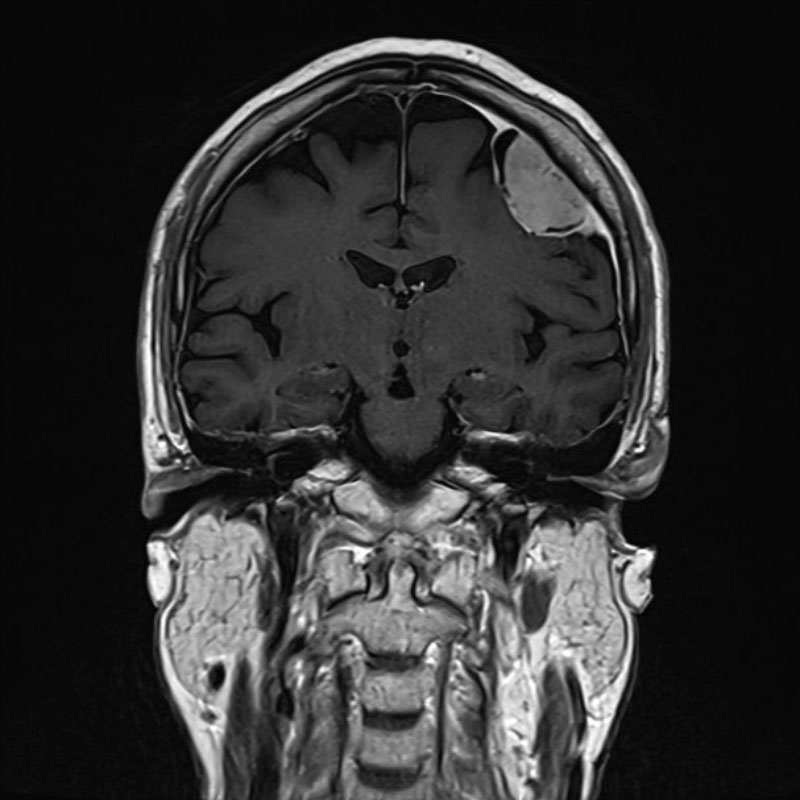

右頭頂葉腫瘍

No.’25_108 手術前1

No.’25_108 手術前2